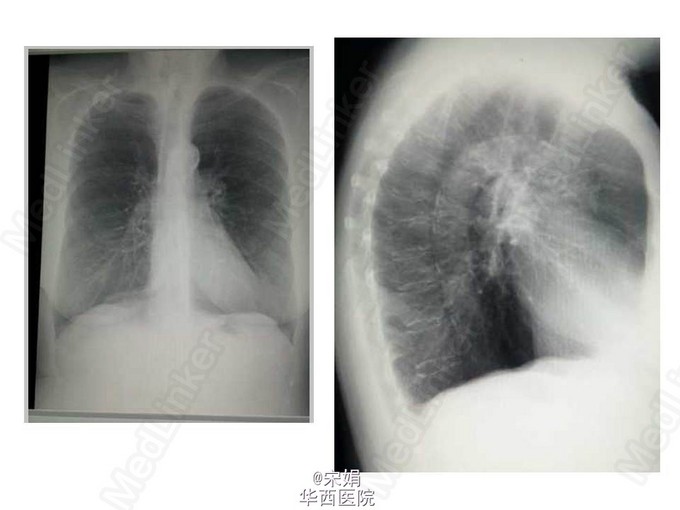

COPD病人 X线典型表现是肺过度充气,可见肺容积增加,肋骨走向变平,肺野透亮度增高。横隔位置低平,心脏悬垂狭长。这个病人的侧位胸片竟然可以清晰的看到主动脉和主动脉弓!